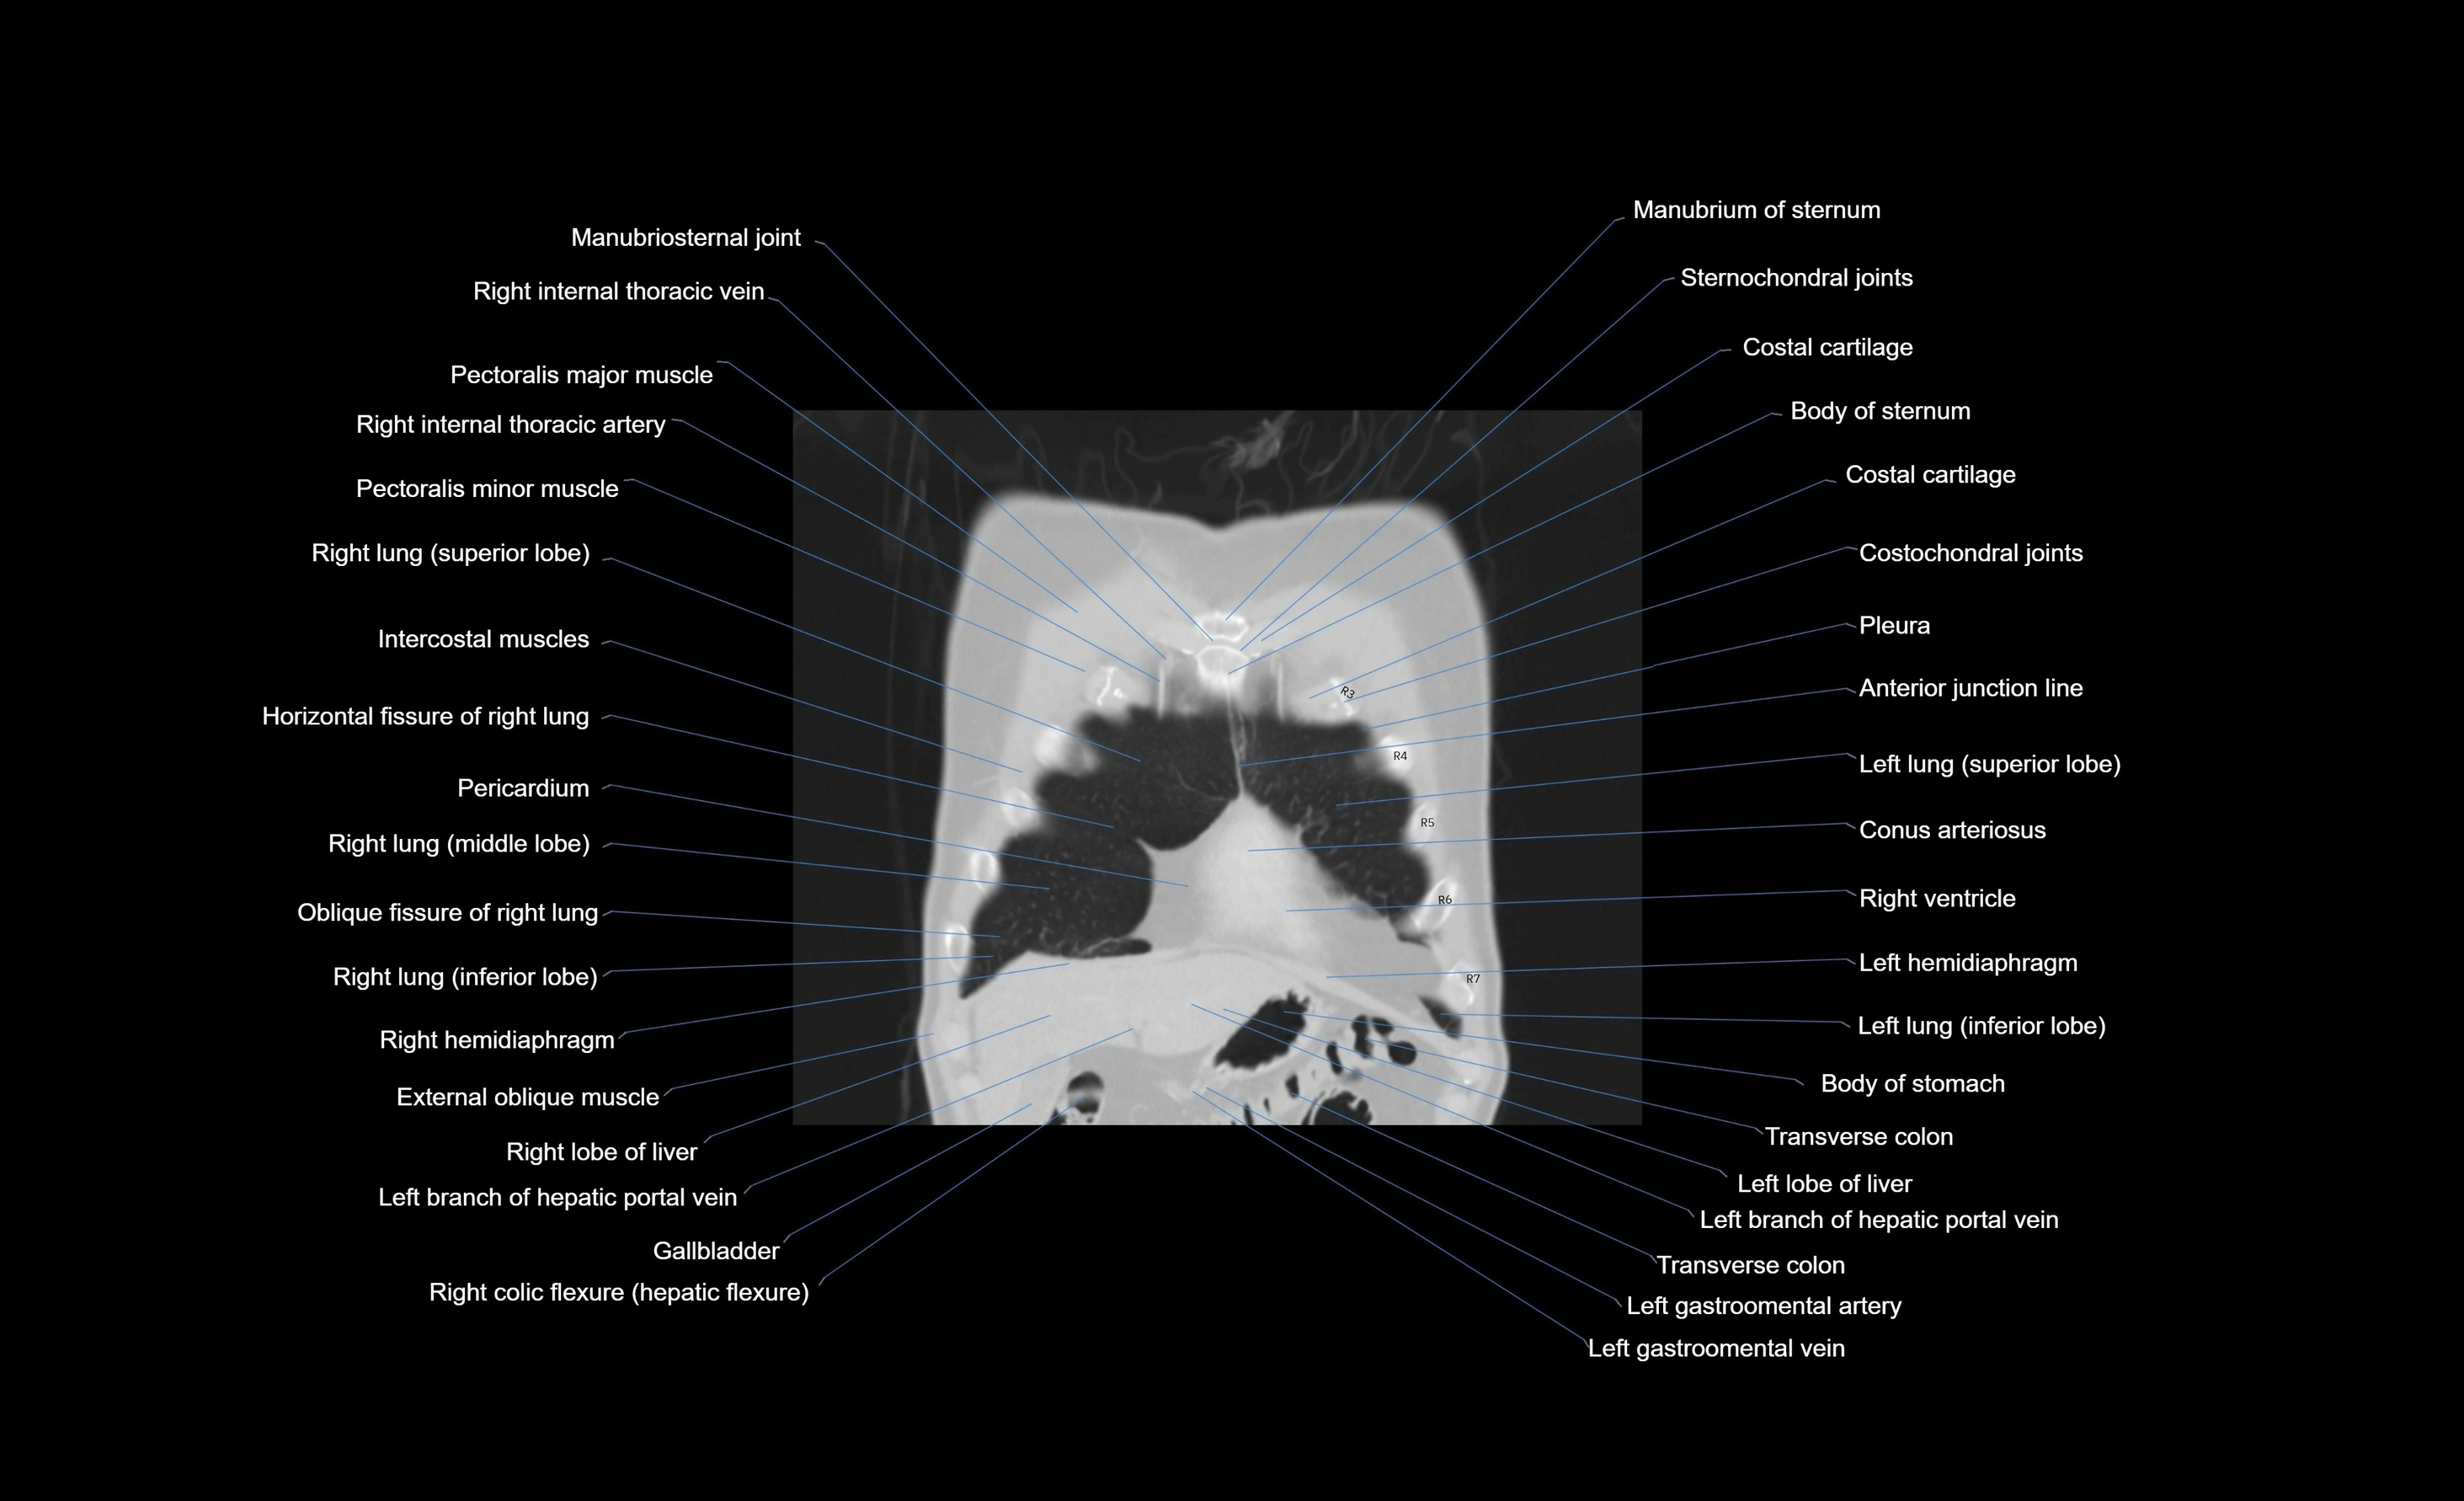

- Body of sternum

- Costal cartilages

- Costochondral joints

- External oblique muscle

- Gallbladder

- Horizontal fissure of right lung

- Intercostal muscles

- Left hemidiaphragm

- Left lung (inferior lobe)

- Manubrium of sternum

- Oblique fissure of right lung

- Pectoralis major muscle

- Pectoralis minor muscle

- Pericardium

- Pleura

- Right hemidiaphragm

- Right internal thoracic artery

- Right internal thoracic veins

- Right lobe of liver

- Right lung (middle lobe)

- Right lung (superior lobe)

- Right ventricle